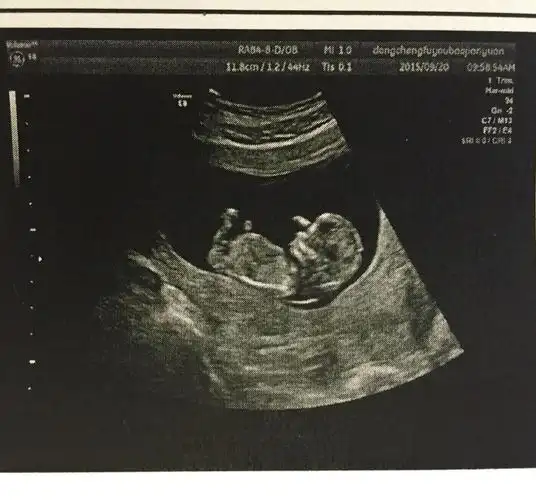

孕12周 4 b超图可见清晰成型胎儿

胎儿十二周发育都有哪些具体的变化有没有图片做对比

胎儿维持生命的器官已经开始工作,如肝脏开始分泌胆汁,已形成完整的肺